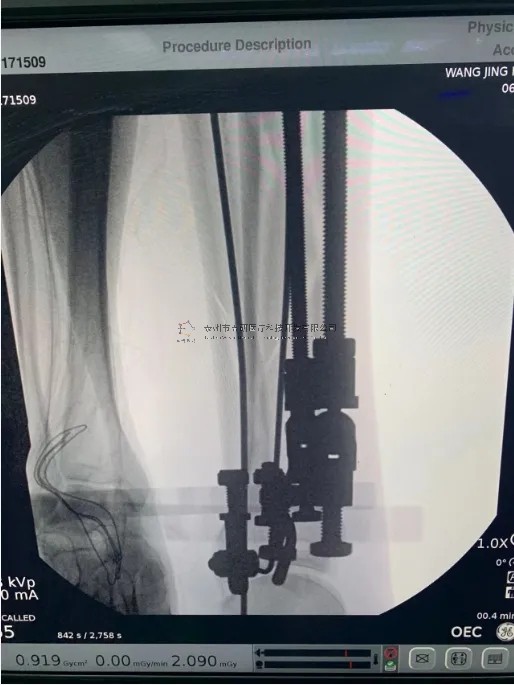

2月份,我們在中國中醫(yī)科學院望京醫(yī)院就有多臺關于外固定支架的手術,以下介紹一則不開刀CO接骨治療小腿骨折典型病例:

【手術資料】